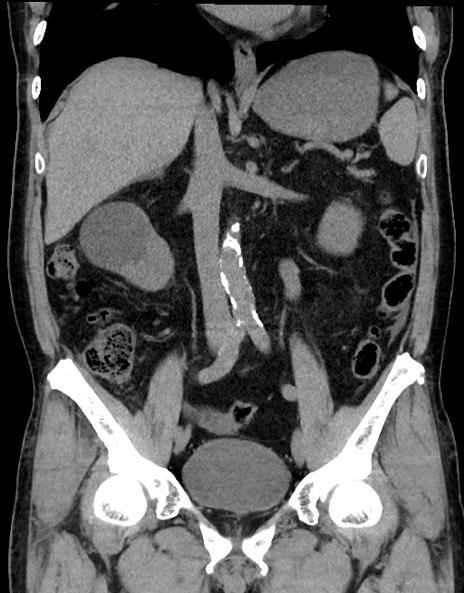

症例15(冠状断像)

【症例】70歳代男性

【主訴】腹痛

【現病歴】今朝から腹痛あり。全体的に痛い。特に左上の方。排ガスが今日はない。冷や汗が出る。

【既往歴】直腸癌術後

【身体所見】左側腹部〜上腹部に圧痛あり。腹膜刺激症状明らかなではない。軽度反跳痛。左下腹部に術後瘢痕あり。

【データ】WBC 7700、CRP 0.02